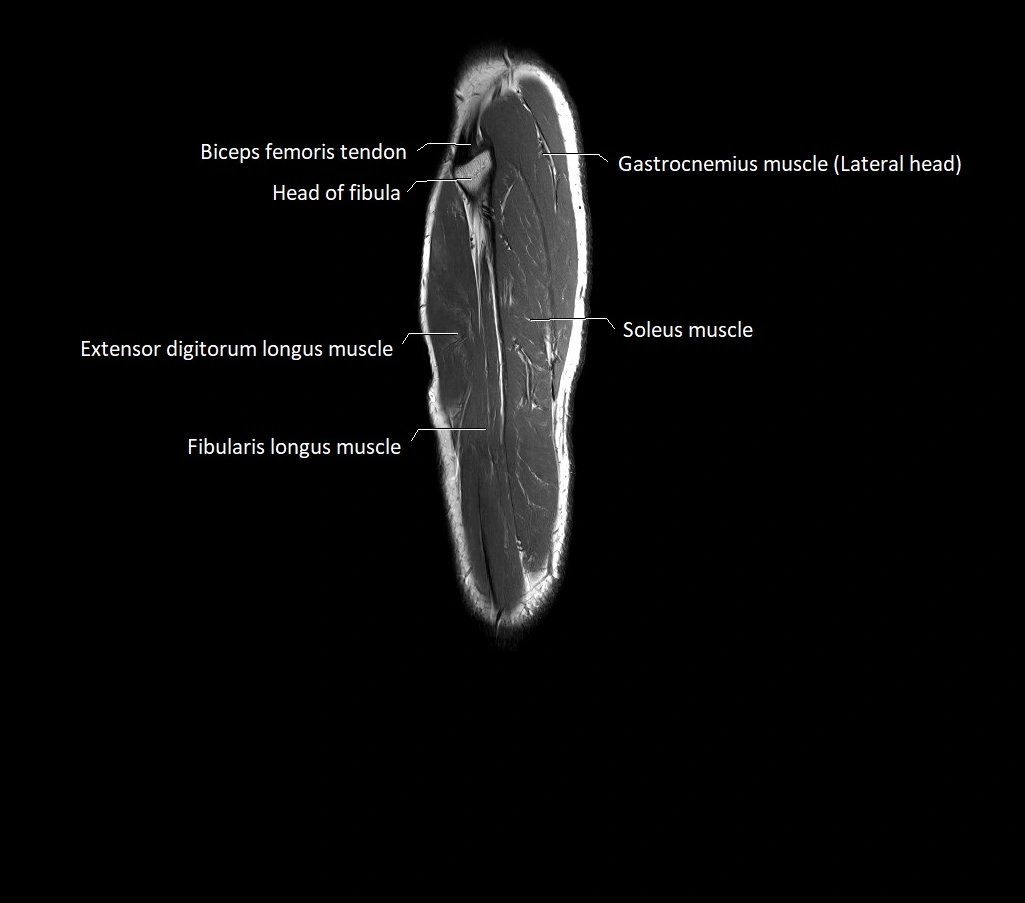

MRI image